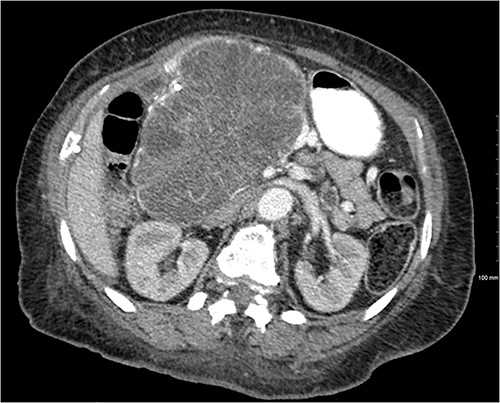

Another abdominal CT was performed redemonstrating the large heterogenous mixed attenuating mass within the right abdomen measuring 14.0 × 10.0 × 13.0 cm likely originating from the pancreatic head with resultant displacement of the PTC anteriorly and to the right with extensive pancreatic ductal dilation (Figs 2 and 3).

Mass effect to abdominal viscera from the 14 × 10 × 13 cm pancreatic head mass.